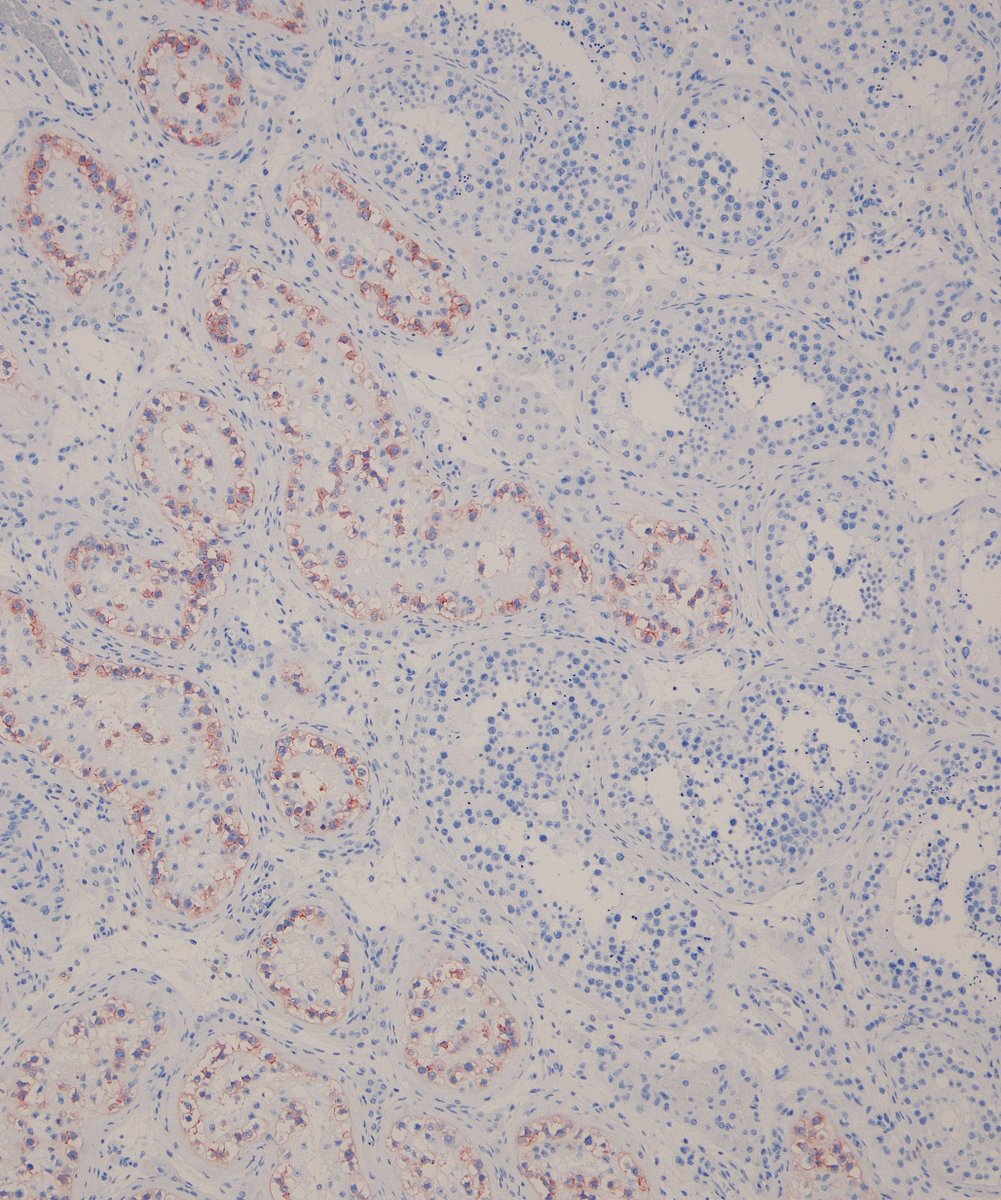

20 yo M. Deep intramuscular calf nodule. SOX-10 +. Loss of SMARCB1 staining. Answer ✅ youtu.be/YrUty8brYHU?si… Digital slides: kikoxp.com/posts/21930 #pathology #pathologists #pathTwitter #dermpath #dermatology #dermatologia #dermtwitter #BSTpath

20 yo M. Deep intramuscular calf nodule. SOX-10 +. Loss of SMARCB1 staining.

Answer ✅ youtu.be/YrUty8brYHU?si…

Digital slides: kikoxp.com/posts/21930

#pathology #pathologists #pathTwitter #dermpath #dermatology #dermatologia #dermtwitter #BSTpath